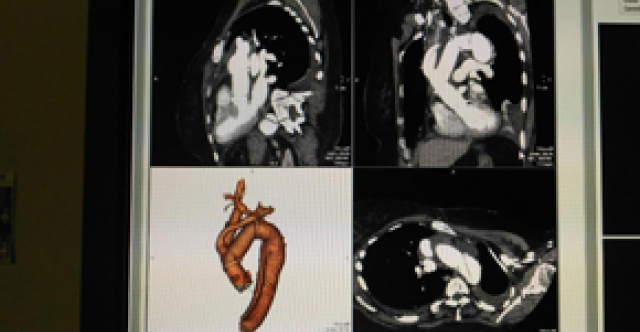

Відділення хірургічного лікування патології аорти та набутих вад серця

Завідувач – Кравченко Віталій Іванович